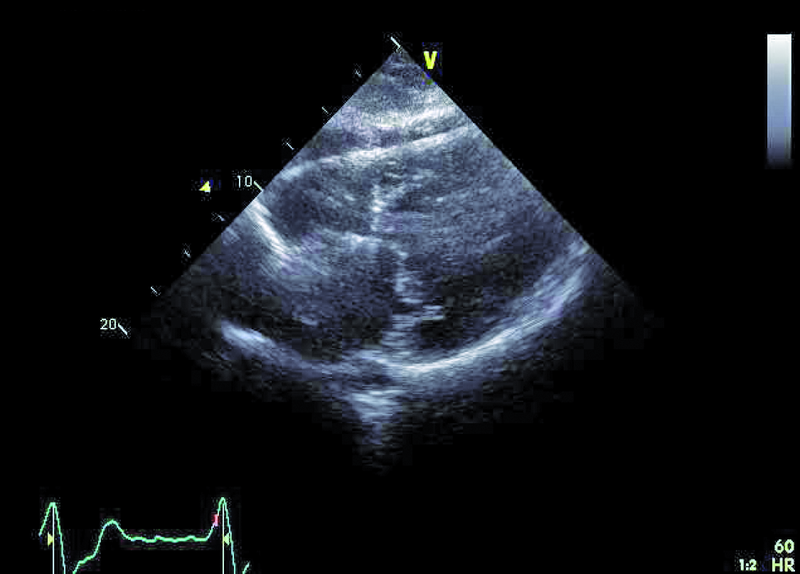

Mężczyzna, lat 35. Jakie patologie można rozpoznać na rycinach?

1. Przerost mięśnia lewej komory (ryc. 1).

2. Przeciek okołozastawkowy – przy przednim brzegu pierścienia zastawki aortalnej (ryc. 1, 2).